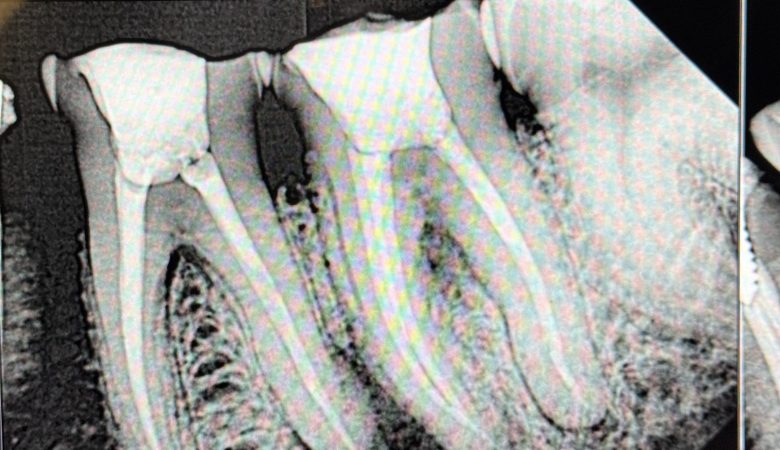

Endodontic Retreatment for Lower 1st molar followed by core build up and Zirconia crown.…